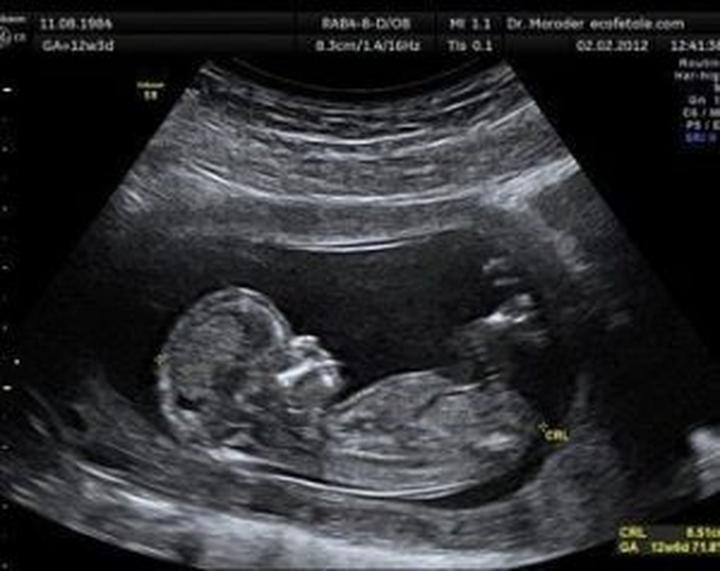

Nie martwcie się jednak, przed wami jeszcze kilka istotnych wizyt! Po pierwszym USG nadchodzi czas kolejnego badania, które odbywa się między 11 a 13 tygodniem. Lekarze podczas tej wizyty sprawdzą genetyczne markery maluszka, a także ocenią ryzyko wystąpienia pewnych nieprawidłowości. Co więcej, warto pamiętać o strefie komfortu – śmiało zadawajcie wszelkie pytania, które przychodzą wam na myśl. Nie czujcie się też jak hipokryci; to zupełnie normalne, że w tym wyczekiwanym czasie pojawiają się wątpliwości!

Przejdźmy do konkretów – według rekomendacji Polskiego Towarzystwa Ginekologów i Położników pełny zestaw badań USG składa się z kilku kluczowych elementów. Oprócz wspomnianego badania we wczesnej ciąży oraz „połówkowego”, mamy także USG w trzecim trymestrze, które dostarcza szczegółowych informacji na temat wzrostu i położenia dziecka. Co więcej, w tej części ciąży wykorzystujemy nowinki technologiczne, takie jak USG 3D i 4D, dzięki którym możemy zobaczyć twarz malucha w ruchu. Wbrew pozorom, to nie tylko dla przyjemności – daje to lekarzowi okazję do obserwacji ewentualnych anomalii, co stanowi kluczowy aspekt dla zdrowia dziecka.

- USG we wczesnej ciąży – potwierdzenie obecności zarodka i bicia serca.

- Badanie połówkowe – analiza anatomii płodu i ocena wzrostu.

- USG w trzecim trymestrze – szczegółowe informacje o położeniu dziecka.

- USG 3D i 4D – możliwość zobaczenia malucha w ruchu i wykrywania anomalii.